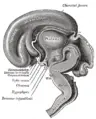

Brain: Hypothalamus

Location of the human hypothalamus

The hypothalamus, also known as the "master gland," is a supervising center in the brain that links the body's two control systems, the nervous system and the endocrine system, via interaction with the pituitary gland (hypophysis). The hypothalamus (from Greek áœ‘Ï€ÎżÎžÎ±Î»Î±ÎŒÎżÏ‚, "under the thalamus") is located below the thalamus, just above the brain stem, and occupies the major portion of the ventral region of the brain known as the diencephalon. The hypothalamus is found in all mammalian brains; in humans, it is roughly the size of an almond.